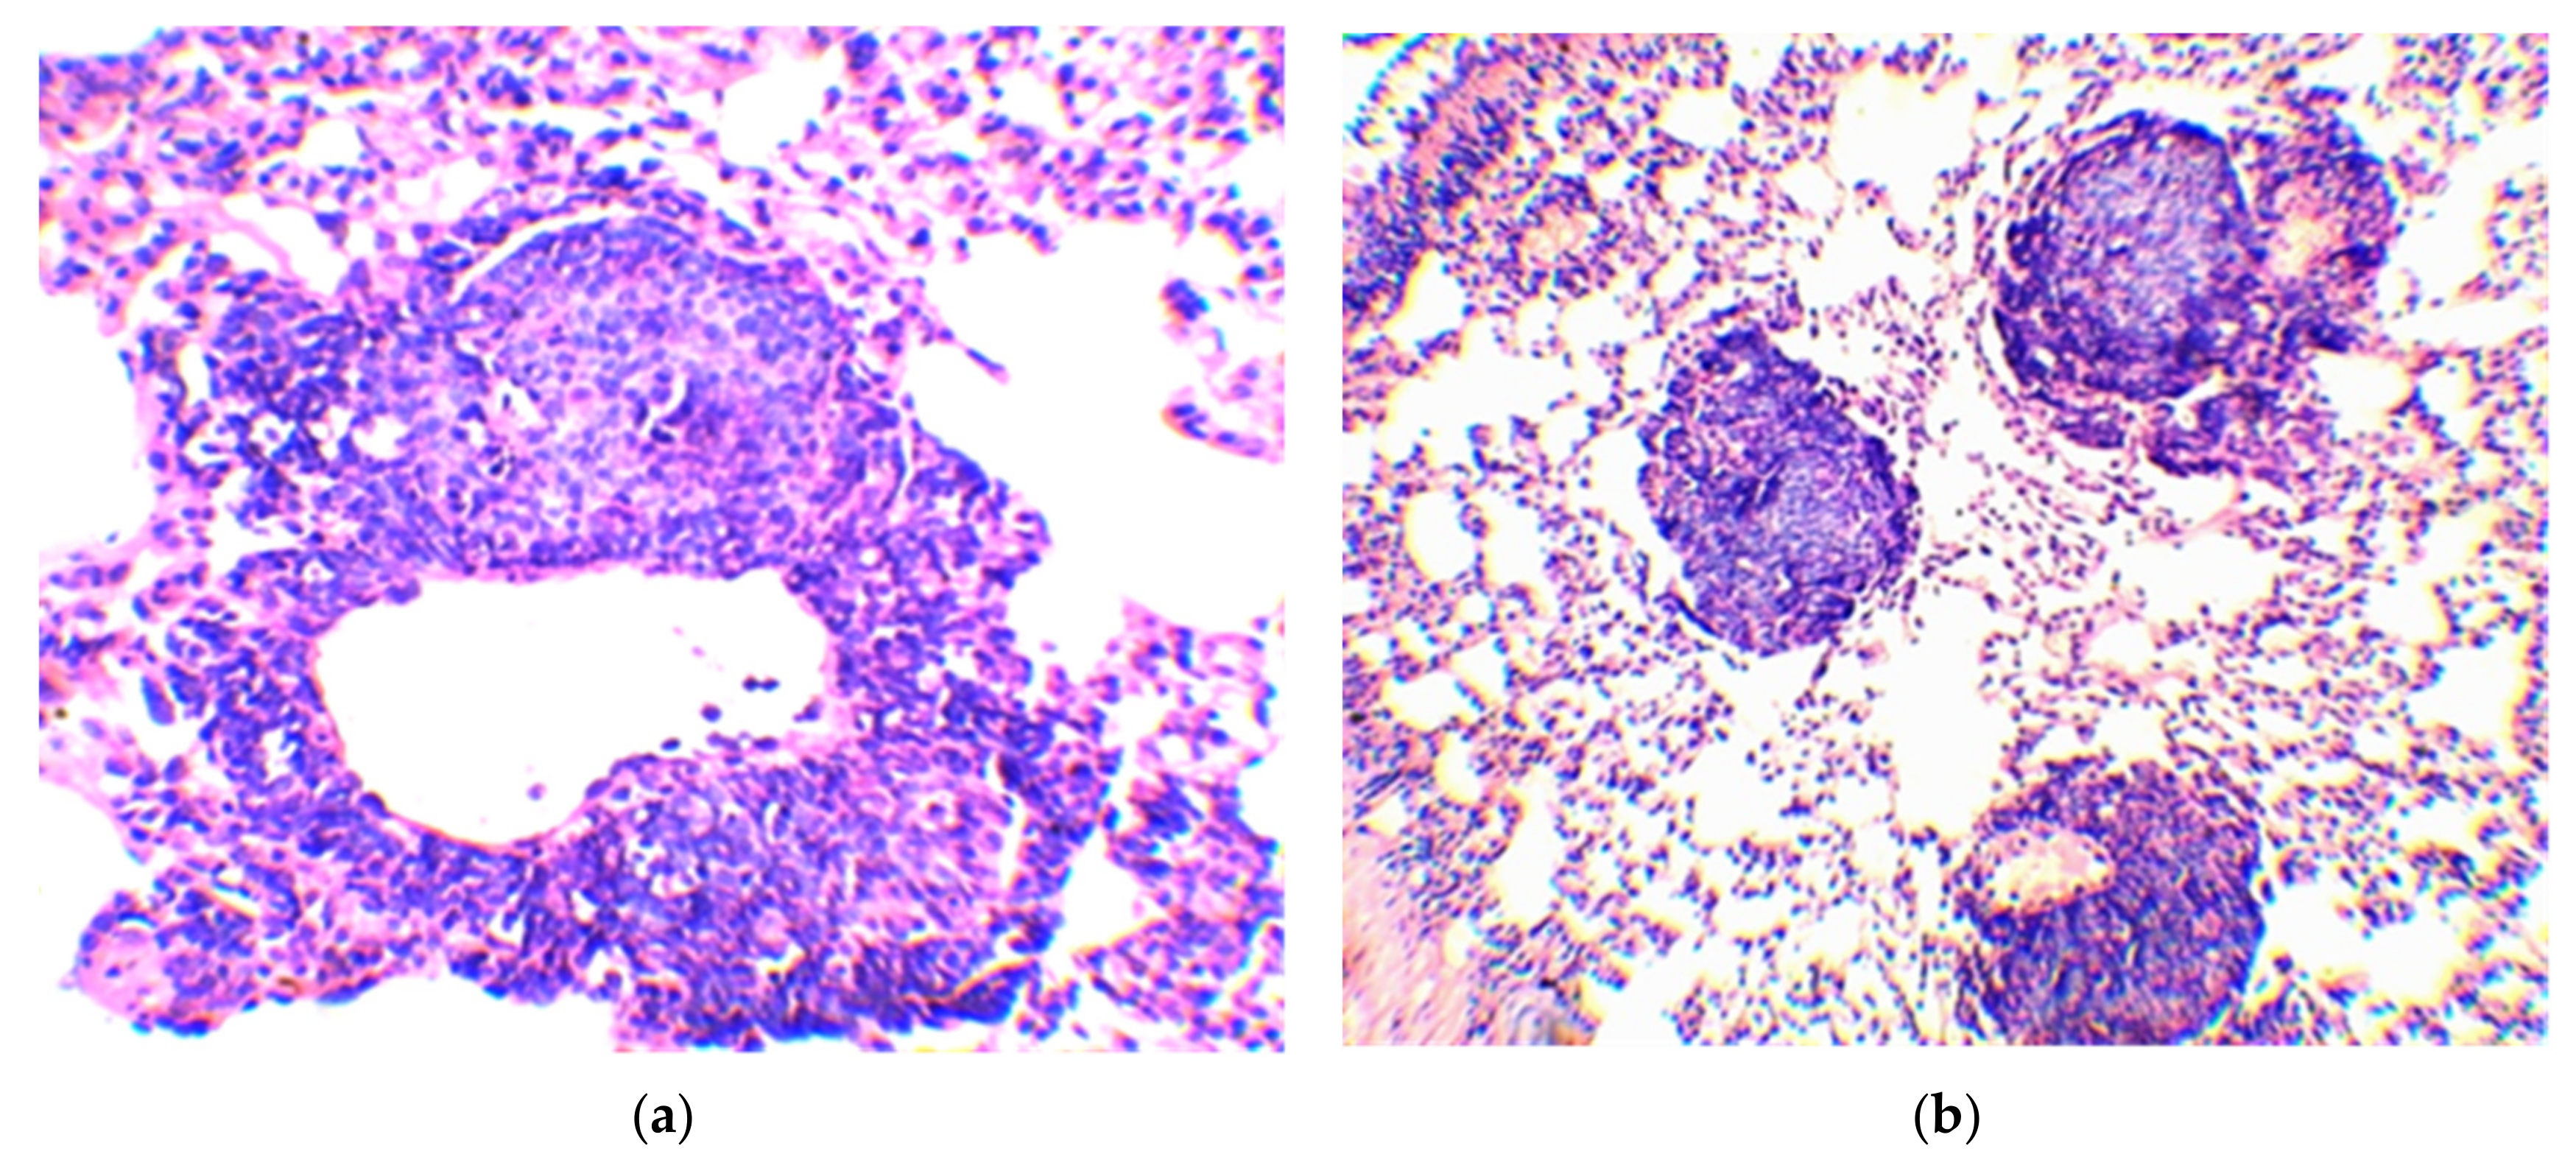

| Group No. | BCG Vaccine | Compound | Mean Follicle Area (µm2) | Mean Follicle Diameter (µm) | Follicle Size Distribution by Diameter (µm) | Number of Follicles of the Same Size (%) |

|---|---|---|---|---|---|---|

| 1 | − | − | 34,103.0 ± 2766.5 | 203.0 ± 8.8 | 70–100 | 3.3 |

| 110–160 | 23.3 | |||||

| 170–220 | 40.0 | |||||

| 230–270 | 26.7 | |||||

| 280–300 | 6.7 | |||||

| 2 | + | Betulinic acid | 37,478.8 ± 4532.1 | 216.3 ± 14.0 | 70–100 | 6.7 |

| 110–160 | 16.7 | |||||

| 170–220 | 33.3 | |||||

| 230–270 | 25.7 | |||||

| 280–300 | 16.7 | |||||

| 3 | + | Betulin | 19,080.7 ± 1905.0 1 | 147.0 ± 9.0 2 | 70–100 | 10.0 |

| 110–160 | 53.5 | |||||

| 170–220 | 36.7 | |||||

| 4 | + | Betulonic acid | 11,458.4 ± 1240.7 2 | 115.7 ± 6.5 2 | 70–100 | 43.3 |

| 110–160 | 46.7 | |||||

| 170–190 | 10.0 | |||||

| 5 | + | − | 20,742.3 ± 2386.4 1 | 155.0 ± 9.1 2 | 70–100 | 13.3 |

| 110–160 | 50.0 | |||||

| 170–220 | 23.4 | |||||

| 230–250 | 13.3 |